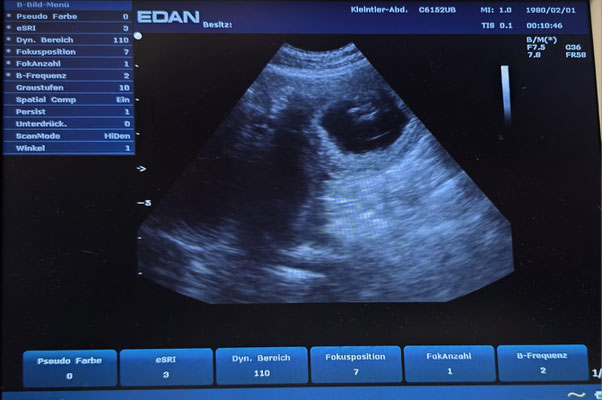

Am 02.09.25 waren wir mit unserer Lillifee zum Ultraschall und was soll ich sagen, wir sind Schwanger